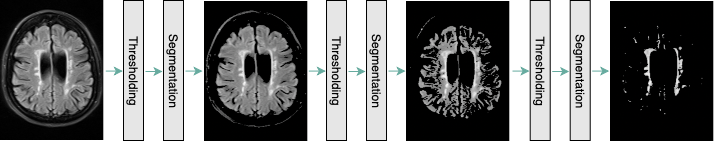

As it is mentioned earlier, the classification task is mainly based on a specific type of white matter lesions. Hence, the CNN model, which can successfully classify patients based on the aforementioned biomarker, should mostly attend to the areas of the input image containing white matter lesions. Consequently, we designed a component for white matter lesion segmentation to be performed on the given MR images. This component is comprised of three steps:

1. 1.

Detecting and removing the background of the image

2. 2.

Removing dark grey periventricular areas along with other dark regions of the brain

3. 3.

Segmenting bright areas of the brain image, which is mainly consisted of white matter lesions (if any)

This process is conducted during each step, and the former output image is passed as the input image of the latter (Fig. 2). It is notable that since this method is performed on each image separately, it can adapt to images with different grayscale distributions. This enables us to segment white matter lesions in all patients regardless of the patient positioning and the device setting.

Refer to caption

Figure 2: The proposed pre-processing method at a glance. Step 1: Removing background of the brain image; Step 2: Removing grey areas of the brain image, as they do not contain the white matter lesion; Step 3: Removing the remaining grey areas in the image and preserving the bright regions, which is mostly formed by White Matter Lesions.